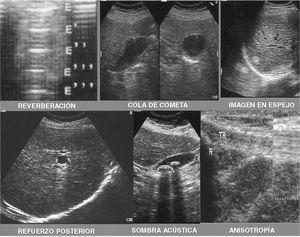

ARTEFACTOS

Son anomalías que aparecen en la imagen y que alteran o falsean la realidad pudiendo inducir a error. Todas las modalidades de imagen tienen artefactos que son únicos de ese sistema. En los sistemas radiográficos, los artefactos degradan las imágenes y reducen su valor diagnóstico. En las imágenes ecográficas los artefactos pueden facilitar la realización del diagnóstico. Los artefactos se pueden clasificar en tres categorías, como la antigua película de Clint Eastwood: el bueno (la sombra, el refuerzo posterior y el artefacto de cola de cometa), el malo (la refracción, la reverberación, los reflectores anisotrópicos, el artefacto sónico de velocidad y el artefacto de haz ancho) y el feo (artefacto de movimiento y ruido eléctrico)13. Es por tanto necesario reconocer cada uno de estos artefactos (fig. 5).

Figura 5. Artefactos ecográficos.

Sombra acústica posterior

Zonas sin ecos que aparecen detrás de estructuras que reflejan todos los ultrasonidos. La imagen ecográfica muestra una zona oscura detrás de una estructura hiperecogénica. Es una interfase muy reflexiva y casi toda la energía del haz sónico incidente sobre ellas se reflejará. Es similar a la sombra que emite un edificio en un día soleado. Ejemplo fisiológico: el hueso. Ejemplo patológico: cálculos o calcificaciones. La sombra sucia es característica del gas dentro de los tejidos. La sombra por refracción o sombra por ángulo crítico se observa cuando se visualizan objetos con superficie curvada como la diáfisis de un hueso largo8,9.

Refuerzo acústico posterior

Aumento en la amplitud de los ecos que se generan tras atravesar una estructura anecoica. La imagen ecográfica muestra una estructura anecoica e inmediatamente detrás de esta aparece una zona hiperecogénica. Se da detrás de estructuras que contienen líquido. Ejemplo fisiológico: la vesícula biliar, un vaso. Ejemplo patológico: un quiste, un derrame8,9.

Artefacto de cola de cometa

Este artefacto es el resultando de la reverberación que se produce dentro de un objeto metálico o vidrio. Se encuentra en cuerpos extraños o en los adenomiomas de pared vesical. La periodicidad de las bandas dentro de la cola de cometa es igual al grosor del objeto. El reconocimiento de este artefacto permite al examinado diagnosticar rápidamente cuerpos extraños metálicos y de vidrio. Se puede establecer con exactitud la posición del objeto, sin embargo no se puede determinar con precisión el tamaño de los objetos relativamente pequeños. Un ejemplo serían los cilindros metálicos o de vidrio9.

Refracción

Es la descripción de estructuras reales en localizaciones falsas. La refracción se produce en las interfases entre sustancias que transmiten el sonido a velocidad diferente como la grasa y el muslo. El haz sonido se "desvía" en estas interfases de forma proporcional a la diferencia de velocidad de transmisión del sonido dentro de los dos materiales y el ángulo de incidencia. La desviación del haz sónico da como resultado la descripción de estructuras profundas a la interfase en una localización errónea. Este artefacto se corrige colocando el ángulo de incidencia tan próximo a los 90º como sea posible.

Reverberación

Artefacto producido cuando los ecos devueltos por una interfase muy reflectante no son captados totalmente por el transductor sino que rebotan en este, vuelven a atravesar el organismo hasta la citada interfase que nuevamente los refleja y así sucesivamente hasta agotar la energía. Cuando la reverberación aparece de forma lineal en trayecto corto se denomina "cola de cometa". Ejemplo fisiológico: el gas gastrointestinal. Ejemplo patológico: burbujas de gas en un absceso, burbujas en la vía biliar, cuerpos extraños metálicos (clip, aguja, etc.).

Anisotropía

Una sustancia anisotrópica es aquella que muestra propiedades diferentes dependiendo de la dirección de la medición. En la ecográfica musculoesquelética los reflectores anisotrópicos más característicos son los tendones. Obviamente esto no es deseable cuando evaluamos la integridad del mismo Las imágenes de los tendones con el transductor en una posición oblicua aumentarán marcadamente el contraste de la imagen. Esta técnica sólo es útil para distinguir los tendones de la grasa de alrededor cuando la ecogenicidad de esta se aproxima a la del tendón9.

Artefacto sónico de velocidad

Los ecógrafos determinan la distancia de un objeto al transductor midiendo el tiempo transcurrido desde que se origina el pulso sónico hasta que regresa al transductor. A esto nos referimos como tiempo de escape. Al calcular la distancia el ecógrafo asume una velocidad del sonido constante, sin embargo esta suposición es falsa. Sufriendo refracciones al atravesar diferentes estructuras un ejemplo de este artefacto sería la diferente velocidad de paso del hígado y grasa tras el diafragma. O en la interfase músculo grasa de los pacientes obesos.

Artefacto del haz ancho

Un haz ultrasónico tiene una anchura que varía de acuerdo con las características de diseño del transductor. Cuando un objeto es más pequeño que la anchura del haz ultrasónico, los ecos descritos en esa localización son una combinación de los ecos del objeto y de los tejidos de alrededor. Este promedio de volumen, como se llama en la tomografía axial computarizada (TAC) o la resonancia magnética nuclear (RMN), puede dar el aspecto de eco dentro de quistes simples, así como eliminar la sombra posterior de las calcificaciones pequeñas. Normalmente, esto no interfiere en el diagnóstico. Sin embargo, en ecografía musculoesquelética, a menudo tratamos con estructuras muy pequeñas.

Artefacto de movimiento

El movimiento del paciente puede degradar las imágenes ecográficas así como las radiografías. La imagen ecográfica es la media de los datos de varias adquisiciones. Cuando se produce un movimiento la imagen es borrosa, lo que algunas veces limita de forma severa su valor diagnóstico.

Ruido eléctrico

Generalmente los ecógrafos están bien aislados del ruido electrónico. Sin embargo algunas circunstancias que pueden originarse de interferencias electromagnéticas de transformadores de alto voltaje u otros equipos degradan las imágenes. Estos artefactos no plantean problemas diagnósticos sino dificultades diagnósticas.

Artefacto en espejo

Se produce cuando el haz de ultrasonidos incide sobre una estructura curvilínea que actúa como interfase especular. En este tipo de interfases los ecos vuelven al transductor cuando la incidencia ha sido perpendicular, pero si no ha sido así algunos pueden volver tras cambiar su trayectoria y rebotar contra otra interfase que los refleje hacia la sonda (sufren retardo por mayor recorrido). Ejemplo fisiológico: diafragma. Parte del hígado se ve reflejada al otro lado del diafragma cuando se sabe que al otro lado está el aire del pulmón. Ejemplo patológico: tumor próximo al diafragma.

Variación en la velocidad de los ultrasonidos

Se produce cuando el haz de ultrasonidos atraviesa una estructura que enlentece su paso. La velocidad media de los ultrasonidos en nuestro organismo es de 1.540 m/seg, pero existen medios, como la grasa, en los que la velocidad se reduce, haciendo que aumente el tiempo de tránsito. Los equipos de ecografía utilizan para los cálculos de distancia una velocidad constante de 1.540 m/seg y si aumenta el tiempo de travesía interpretarán que la distancia es mayor que la real. Esto sucede en la "imagen de diafragma partido": si un tumor con alto contenido graso se encuentra justo antes del diafragma, se interpretará un mayor diámetro del tumor, lo que hará aparecer la parte del diafragma situada por detrás a mayor distancia de la real. El diafragma aparece partido en esa zona. La grasa, además de ralentizar la velocidad de los ultrasonidos, los absorbe y refleja en gran cantidad, haciendo que las zonas profundas aparezcan con pocos ecos y baja amplitud, es decir, produce atenuación posterior. Este fenómeno es común en la infiltración grasa hepática.